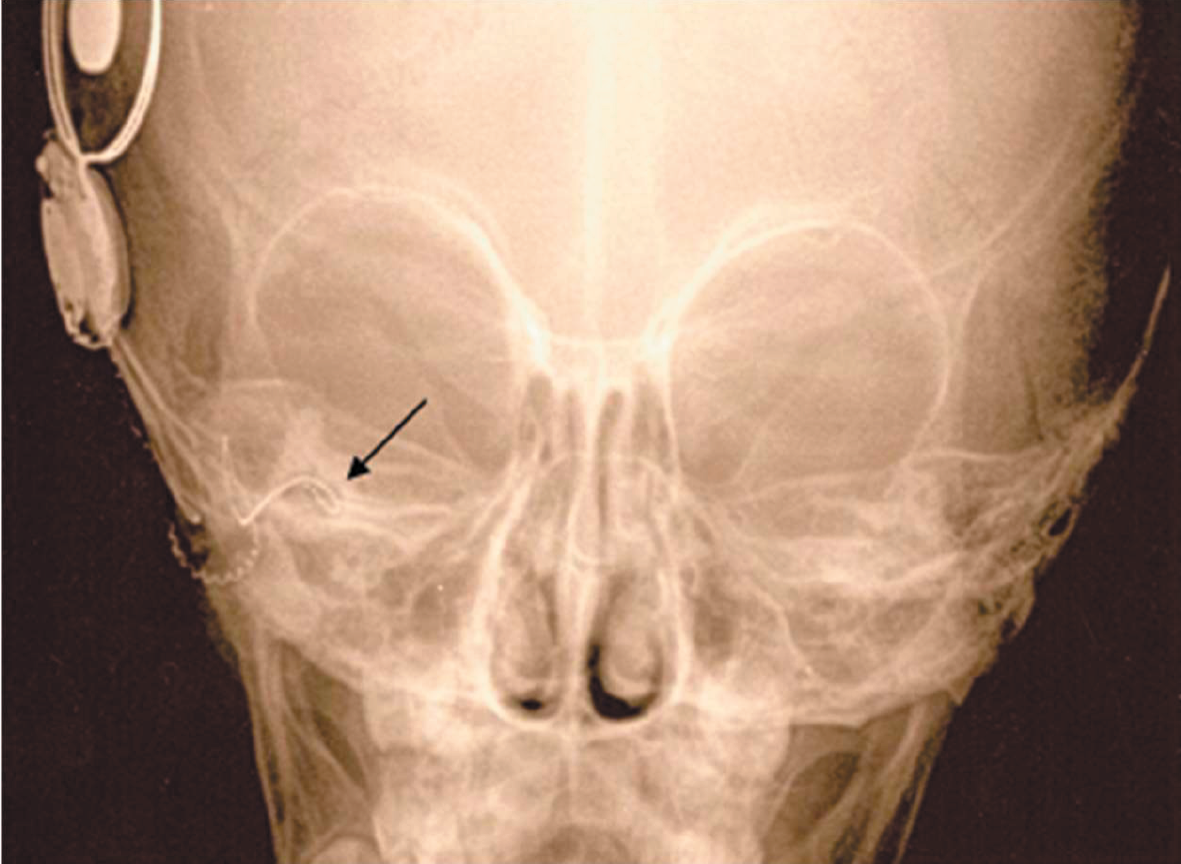

По данным различных авторов, у 20% детей с сенсоневральной тугоухостью или глухотой по результатам компьютерной томографии определяются аномалии строения височных костей. Кохлеарная имплантация при наличии кохлеовестибулярных аномалий сопряжена с рядом трудностей. К ним относятся особенности выполнения кохлеостомии и размещения электрода внутри улитки, риск повреждения лицевого нерва из-за его аномального расположения и его аберрантная стимуляция в послеоперационном периоде, интраоперационная ликворея, что может привести к развитию бактериального менингита в послеоперационном периоде, а также опасность проникновения электрода во внутренний слуховой проход. В данной работе представлен наш способ выполнения кохлеарной имплантации при аномалии развития внутреннего уха – общей полости. Способ расширяет возможности кохлеарной имплантации для восстановления слухового восприятия у пациентов с данной патологией.